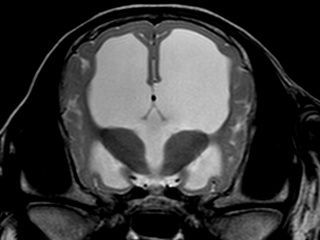

Pour compléter le scanner, le CHV dispose d’une IRM haut champ (1,5T) ORIAN, particulièrement performante pour :

- Cerveau et moelle épinière (épilepsie, AVC, tumeurs, hernies discales, myélopathies).

Notre IRM présente des gradients élevés ainsi qu'une grande ouverture de tunnel permettant de réduire les temps d'acquisition et d'augmenter la résolution spatiale de nos images.